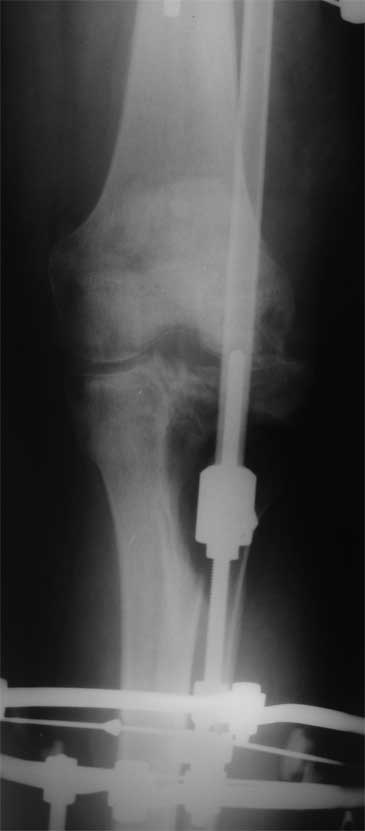

2. Хотелось бы увидеть снимки раннего периода, лучше после травмы, а также КТ. Интересует целостность плато б/б кости. По представленным

снимкам возникает подозрение, что наружный мыщелок отделен. Или это так кажется?

> Хотелось бы увидеть снимки раннего периода, лучше после травмы, а также КТ. Интересует целостность плато б/б кости. По представленным

- нет, скорее всего не кажется, вероятно он отделен, но, скорее всего живой и неподвижный (иначе рассосался бы)